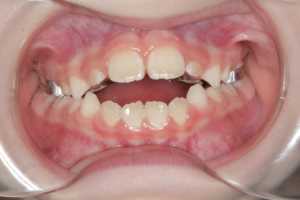

1. Резкое сужение верхней челюсти

2. Большой дефицит места для постоянных зубов

Показания к использованию ортодонтического аппарата Хааса:

- Скученное положение резцов

- Сужение верхней челюсти

- Двухсторонний перекрестный прикус

🔹Резкое сужение верхней челюсти

🔸Большой дефицит места для постоянных зубов

🔹Перекрестный прикус